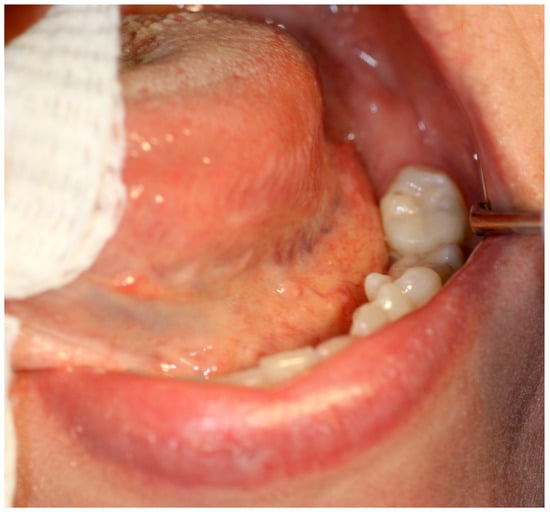

2. Case Report